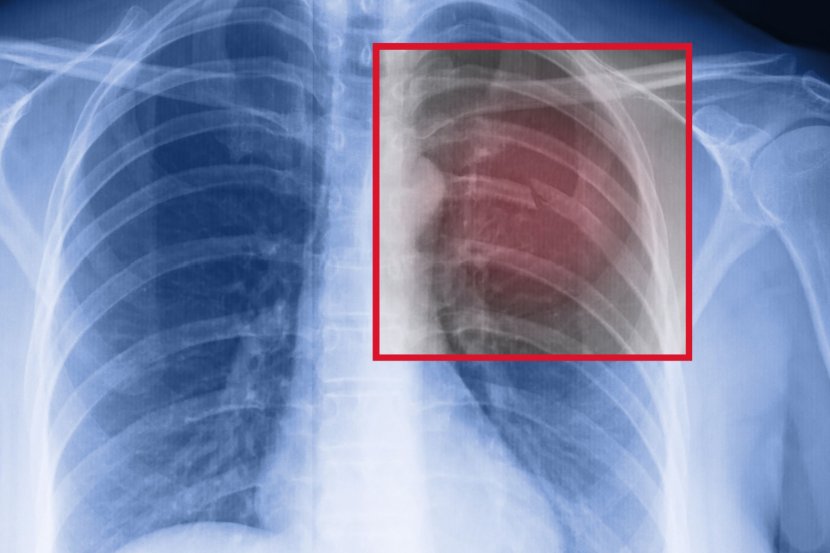

• jedna od 5 beba dobije upalu pluća (infekciju pluća)

• pneumotoraks/prisustvo vazduha u plućnoj maramici